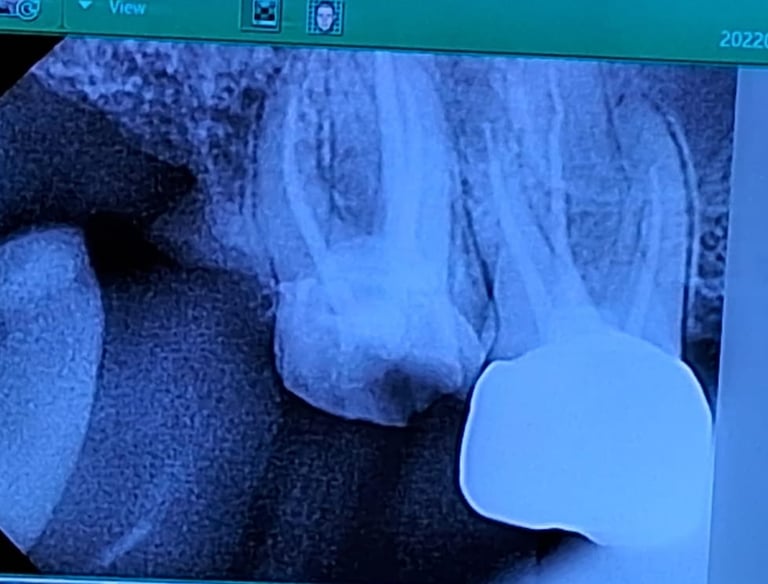

Root Canal Dentistry

Root canal treatment removes infected pulp from inside the tooth, cleans and seals the area to prevent reinfection, and helps save the natural tooth.